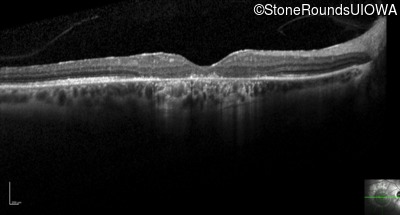

Optical Coherence Tomography - Right - 10/125 +1 sc

Exemplar / OCT Stack